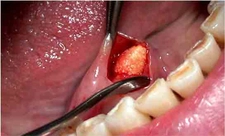

Beze, tıpta "hidradenit suppurativa" olarak bilinen, genellikle ciltte iltihaplı nodül ve apselerin oluşumuyla karakterize bir hastalıktır. Bu durum, özellikle ter bezlerinin yoğun olduğu bölgelerde, yani koltuk altı, kasık, kalça ve meme altı gibi yerlerde meydana gelir. Beze, genellikle ciltte ağrılı lezyonlar, iltihap ve kötü bir koku ile birlikte seyreder. Bu makalede, bezelerin belirtileri, tanı yöntemleri ve tedavi seçenekleri detaylı bir şekilde ele alınacaktır. Beze BelirtileriBeze belirtileri genellikle aşağıdaki şekilde sıralanabilir:

Hidradenit suppurativa, çoğu zaman diğer cilt hastalıklarıyla karıştırılabileceği için, doğru tanı koymak oldukça önemlidir. Tedavi SeçenekleriBeze tedavisi, hastalığın evresine ve şiddetine bağlı olarak değişiklik göstermektedir. Genel olarak tedavi yöntemleri aşağıdaki gibidir: